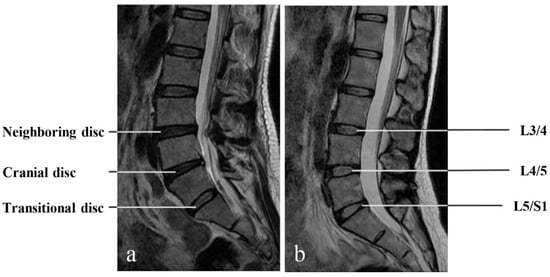

- The Transitional Disc

- The cranial disc

- The neighboring disc